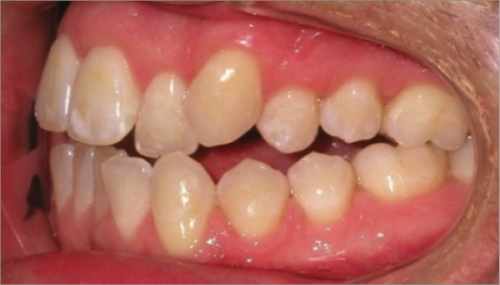

30 year old male:

Diagnosis:

- Upper and lower crowding

- Narrow upper & lowerarch forms

- Open bite

Treatment:

- Invisalign

- Non-Extraction

- 27 months